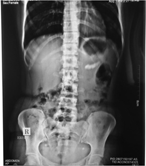

Lumbar vertebral body and pars fractures following laminectomy

Akshay Yadhati and others

Journal of Surgical Case Reports, Volume 2017, Issue 2, February 2017, rjx007, https://doi.org/10.1093/jscr/rjx007